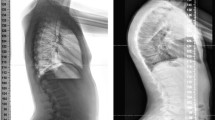

Deformity in adolescent thoracic spine has high prevalence worldwide. The objective of this work was to study the biomechanical behavior on the thoracic spines of adolescents under asymmetric ligament load in kyphosis and rectified kyphosis. Two finite element models of an adolescent thoracic segment, T5–T10, were generated with every bone component, intervertebral discs, the flavum, intertransverse and supraspinous ligaments. The three-dimensional geometry of the T5-T10 was generated with Autodesk®Maya®, and HyperMesh® version 14.0 was used to generate the finite element models. Asymmetric ligament load of 10 N was applied in the T8–T9, with and without axial load of 400 N in the T5 vertebra. Rectified kyphosis showed the highest rotational displacement of the T8–T9 unit: 0.16° with axial load and asymmetric ligament load, and 0.22° with asymmetric ligament load alone. Kyphosis exhibited rotational displacement of 0.11° and 0.12°, respectively, for the same load conditions. Rectified kyphosis subjected to an asymmetric ligament force showed greater inoperability of the facet joints, and therefore greater vulnerability to vertebral rotation. The results suggest the need for greater attention to the vertebral assessments in the sagittal plane, beginning from the growth spurt period, to adopt preventive therapeutic in vertebral deformities such as adolescent idiopathic scoliosis.